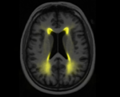

Average Leukoaraiosis projection

Explore the first component of the model